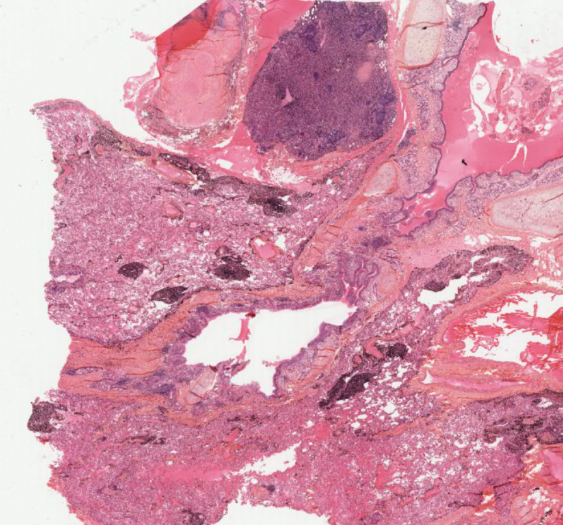

细胞和组织的适应与损伤

感染性藏毛囊肿